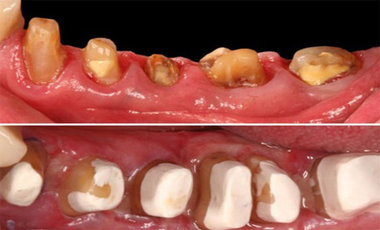

Bundan başqa, travma, ciddi karioz zədələnmə, normadan artıq preparasiya (diş yonulması) və s. nəticəsində diş tacının böyük ölçüdə dağılması zamanı bu dişlərin üzərinə qapaq, körpü konstruksiyalarının hazırlanması və ya bu dişlərin çıxan diş konstruksiyaları üçün (məsələn: teleskopprotezlər) fiksasiya elementi olaraq hazırlanması mümkün olmur. Buna səbəb diş toxumasının normadan artıq dağılmasıdır. Bu zaman tətbiq edilən metodlardan ən başlıcası diş tacının cərrahi uzadılmasıdır. Bu metodun tətbiqi ilə sümük müəyyən miqdarda uzaqlaşdırılaraq dişin tac hissesi uzadılmış olur. Nəticədə protetik olaraq yararsız diş yararlı duruma gətirilir.